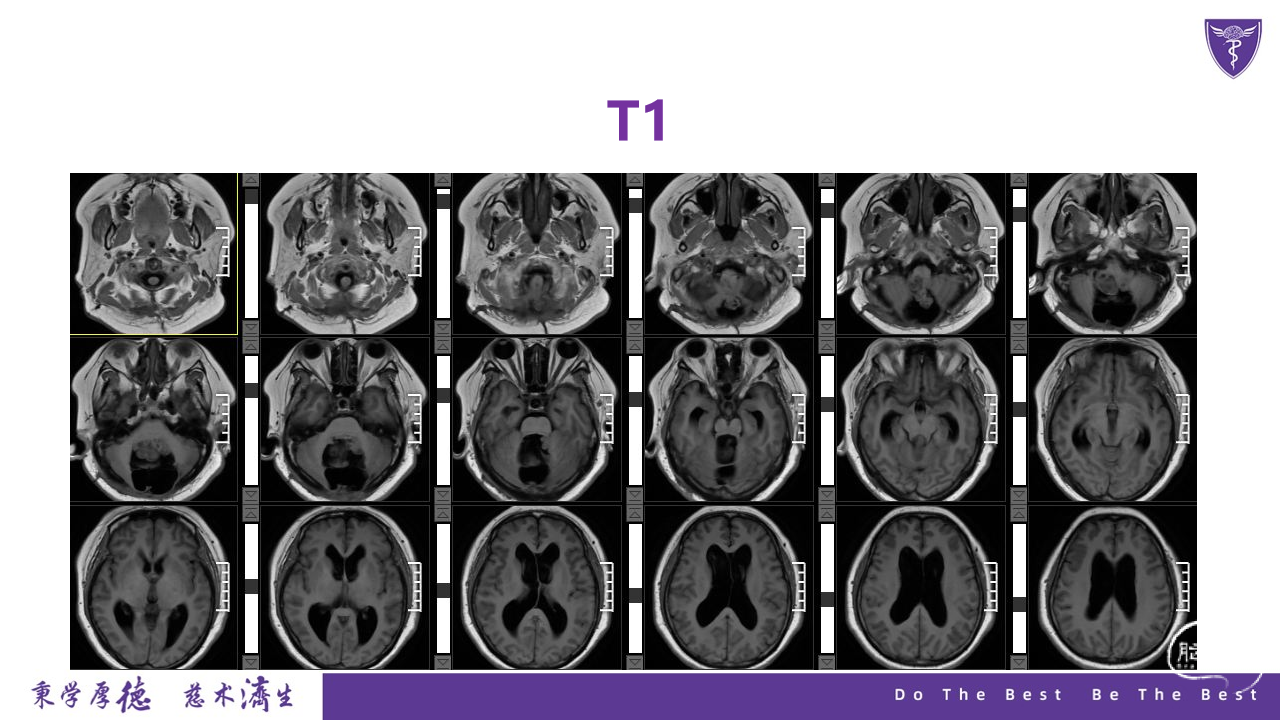

王杰教授团队:四脑室复发室管膜瘤切除术